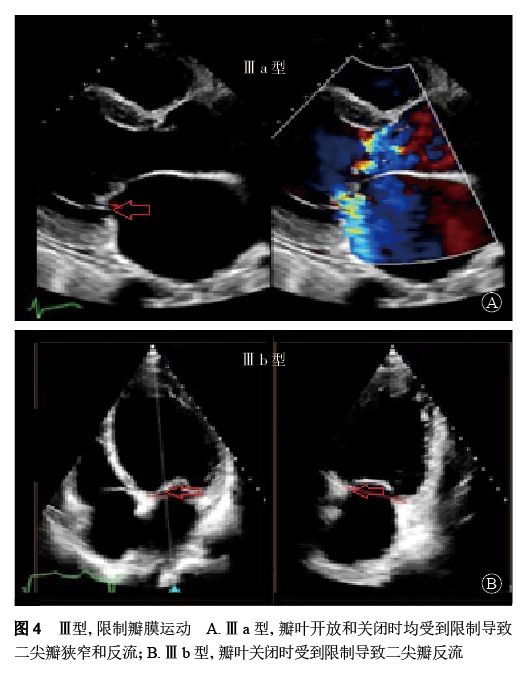

Ⅲ型:瓣叶活动受限的瓣膜功能异常(图4)。在Ⅲ型功能失调中,Ⅲa类指一个或多个瓣叶的运动在瓣叶开放或关闭时受到限制导致不同程度的狭窄或反流(瓣膜及瓣下组织增厚或钙化);Ⅲb类指一个或多个瓣叶的运动在瓣叶关闭时受到限制导致的反流(此类病变多为缺血性导致)。